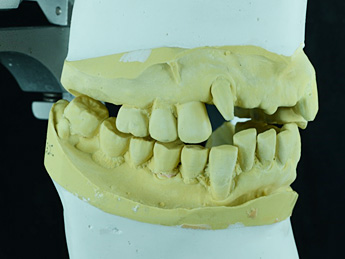

診断用ワックスアップです。

プロビジョナルレストレーションに置き換え、適正な咬み合わせに調整しています。